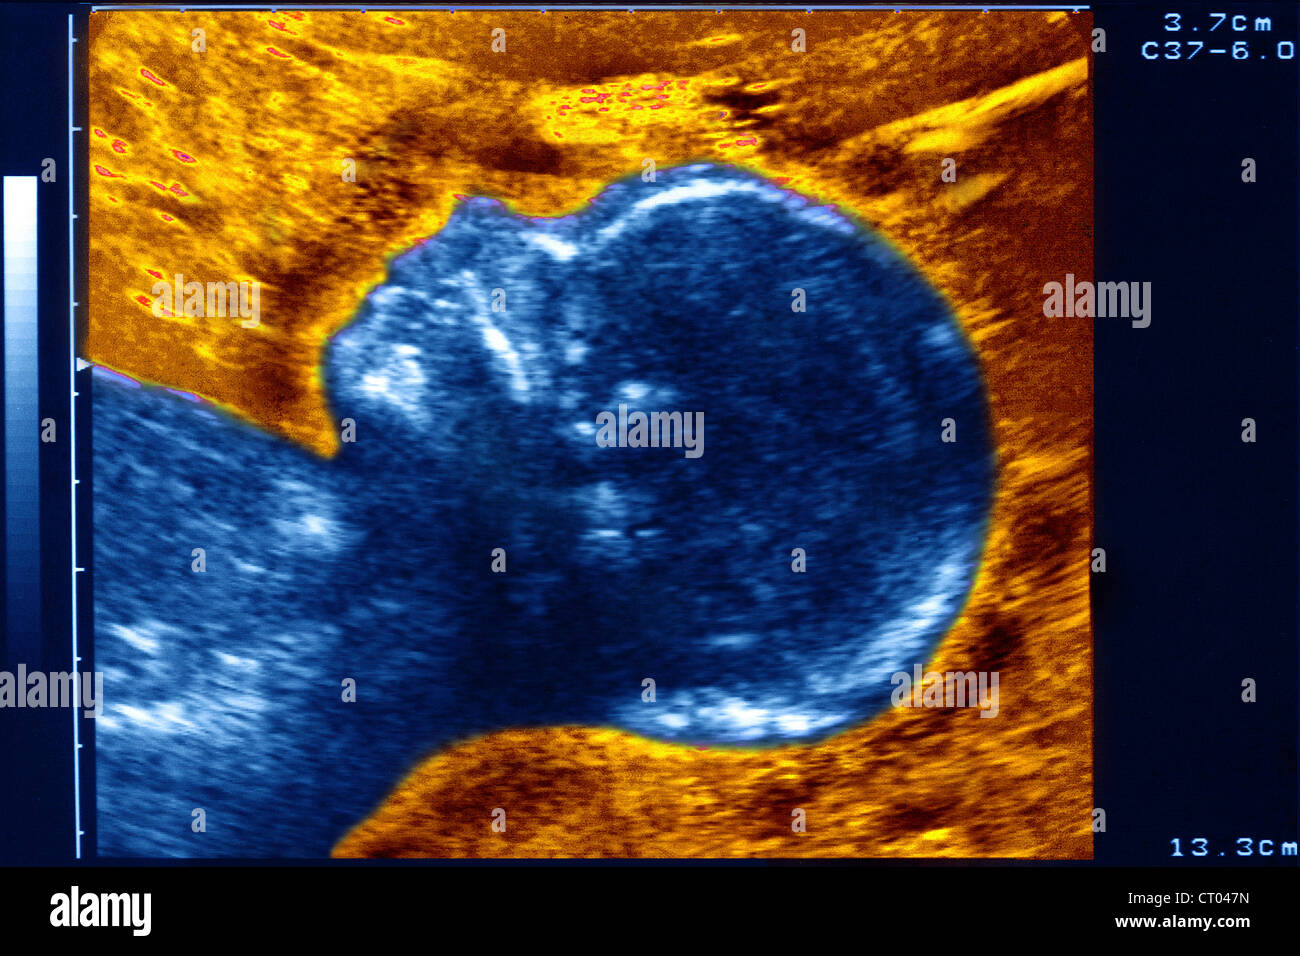

A Screenshot of the Ultrasound Screen in Blue Tones, Where You Can See Skeleton Face Ultrasound The different sutures and fontanelles are depicted in the coronal ( a ), superior ( b ), and lateral ( c ) views of the skull: 3d ultrasound is an important tool for the evaluation of the fetal face in the first trimester. Five basic views are used to assess the fetal head and neck: 2, frontal or metopic suture;. Skeleton Face Ultrasound.

From www.mirror.co.uk